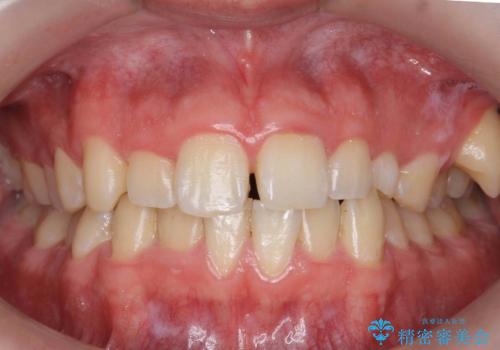

[ 前歯のねじれ・がたつき ] マウスピース矯正

![[ 前歯のねじれ・がたつき ] マウスピース矯正の症例 治療前](https://seimitsushinbi.jp/wp/wp-content/uploads/2024/02/4007c6479f6bce11863dcdd32ed5e39b-500x350.jpg?v=1708502552)

![[ 前歯のねじれ・がたつき ] マウスピース矯正の症例 治療後](https://seimitsushinbi.jp/wp/wp-content/uploads/2024/02/e7a01485e4f4dd0da04705fde4cc34cc-500x350.jpg?v=1708502585)

インビザライン モニター治療 前歯のねじれをまっすぐに